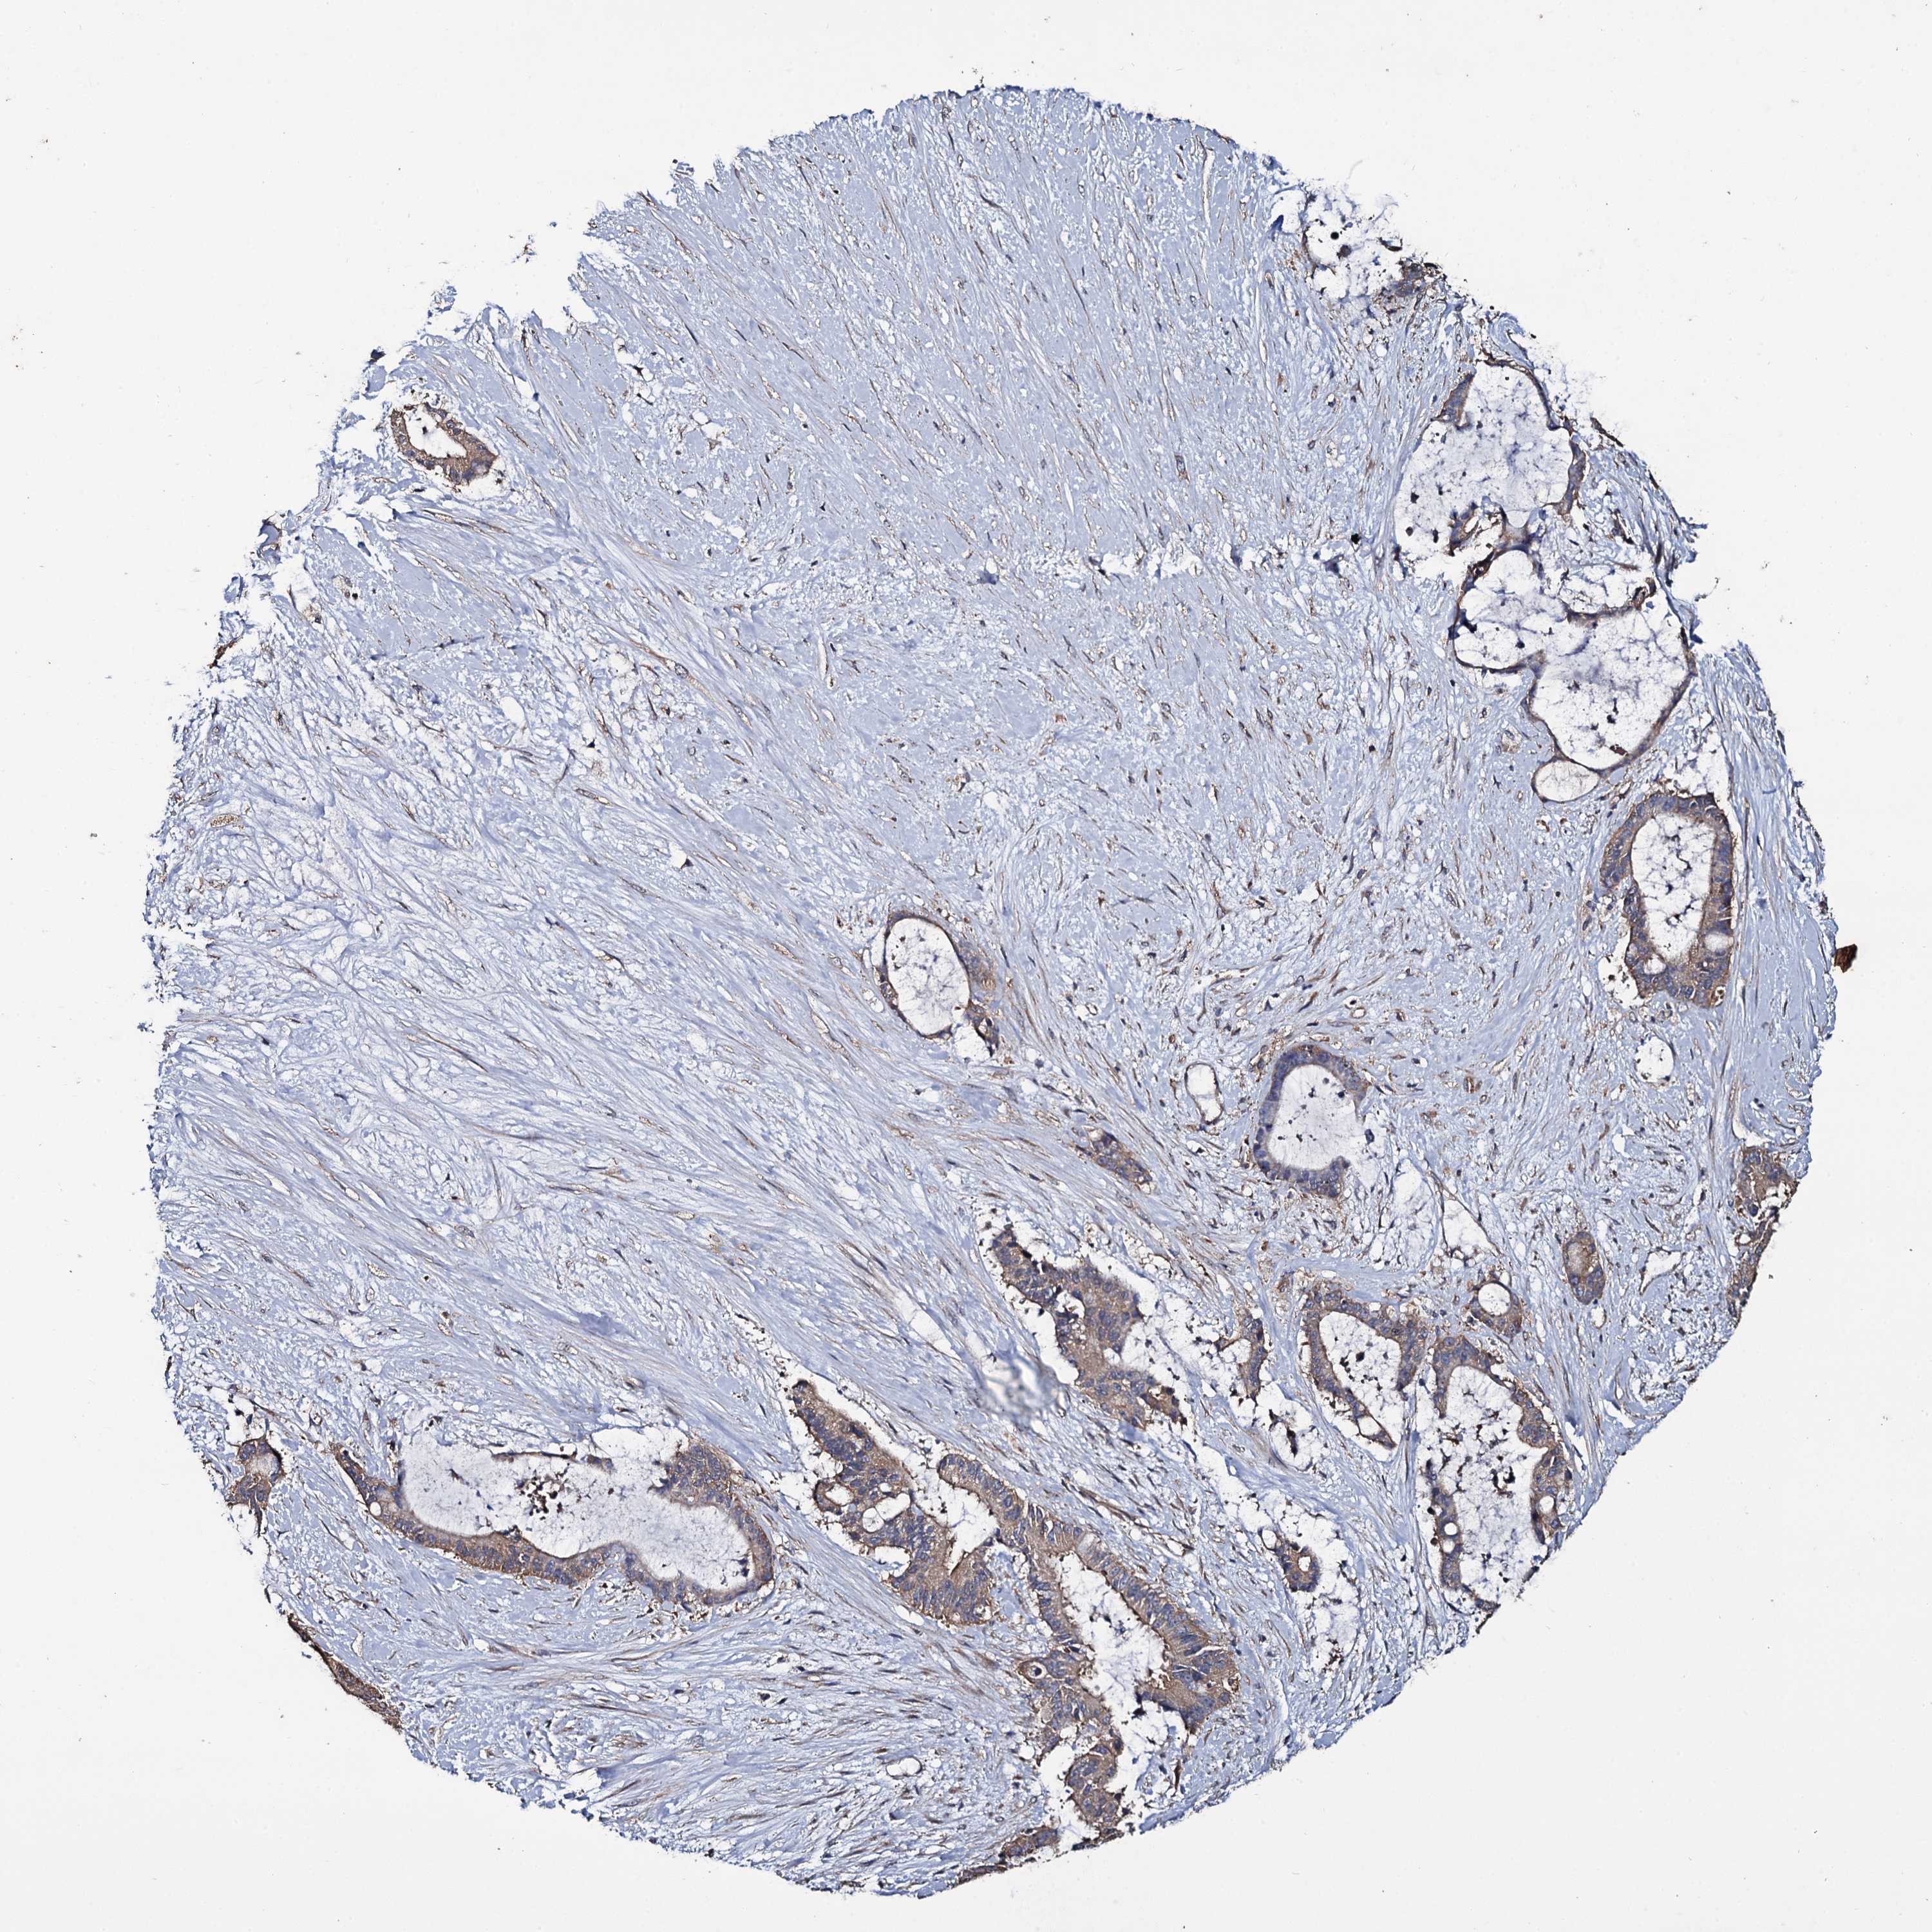

LIVER CANCER - Protein expressioni

A mouse-over function shows sample information and annotation data. Click on an image to view it in a full screen mode. Samples can be filtered based on level of antibody staining by selecting one or several of the following categories: high, medium, low and not detected. The assay and annotation is described here.

Note that samples used for immunohistochemistry by the Human Protein Atlas do not correspond to samples in the TCGA dataset.

Antibody stainingi

Antibody staining in the annotated cell types in the current human tissue is reported as not detected, low, medium, or high, based on conventional immunohistochemistry profiling in selected tissues. This score is based on the combination of the staining intensity and fraction of stained cells.

Each image is clickable and will lead to virtual microscopy that enables deeper exploration of all samples and also displays staining intensity scores, fraction scores and subcellular localization as well as patient and tissue information for each sample.

Antibody HPA039806

Antibody HPA040369

Staining

High

Medium

Low

Not detected

Intensity

Strong

Moderate

Weak

Negative

Quantity

>75%

75%-25%

<25%

None

Location

Nuclear

Cytoplasmic/membranous

Cytoplasmic/membranous,nuclear

Cholangiocarcinoma

Carcinoma, Hepatocellular, NOS